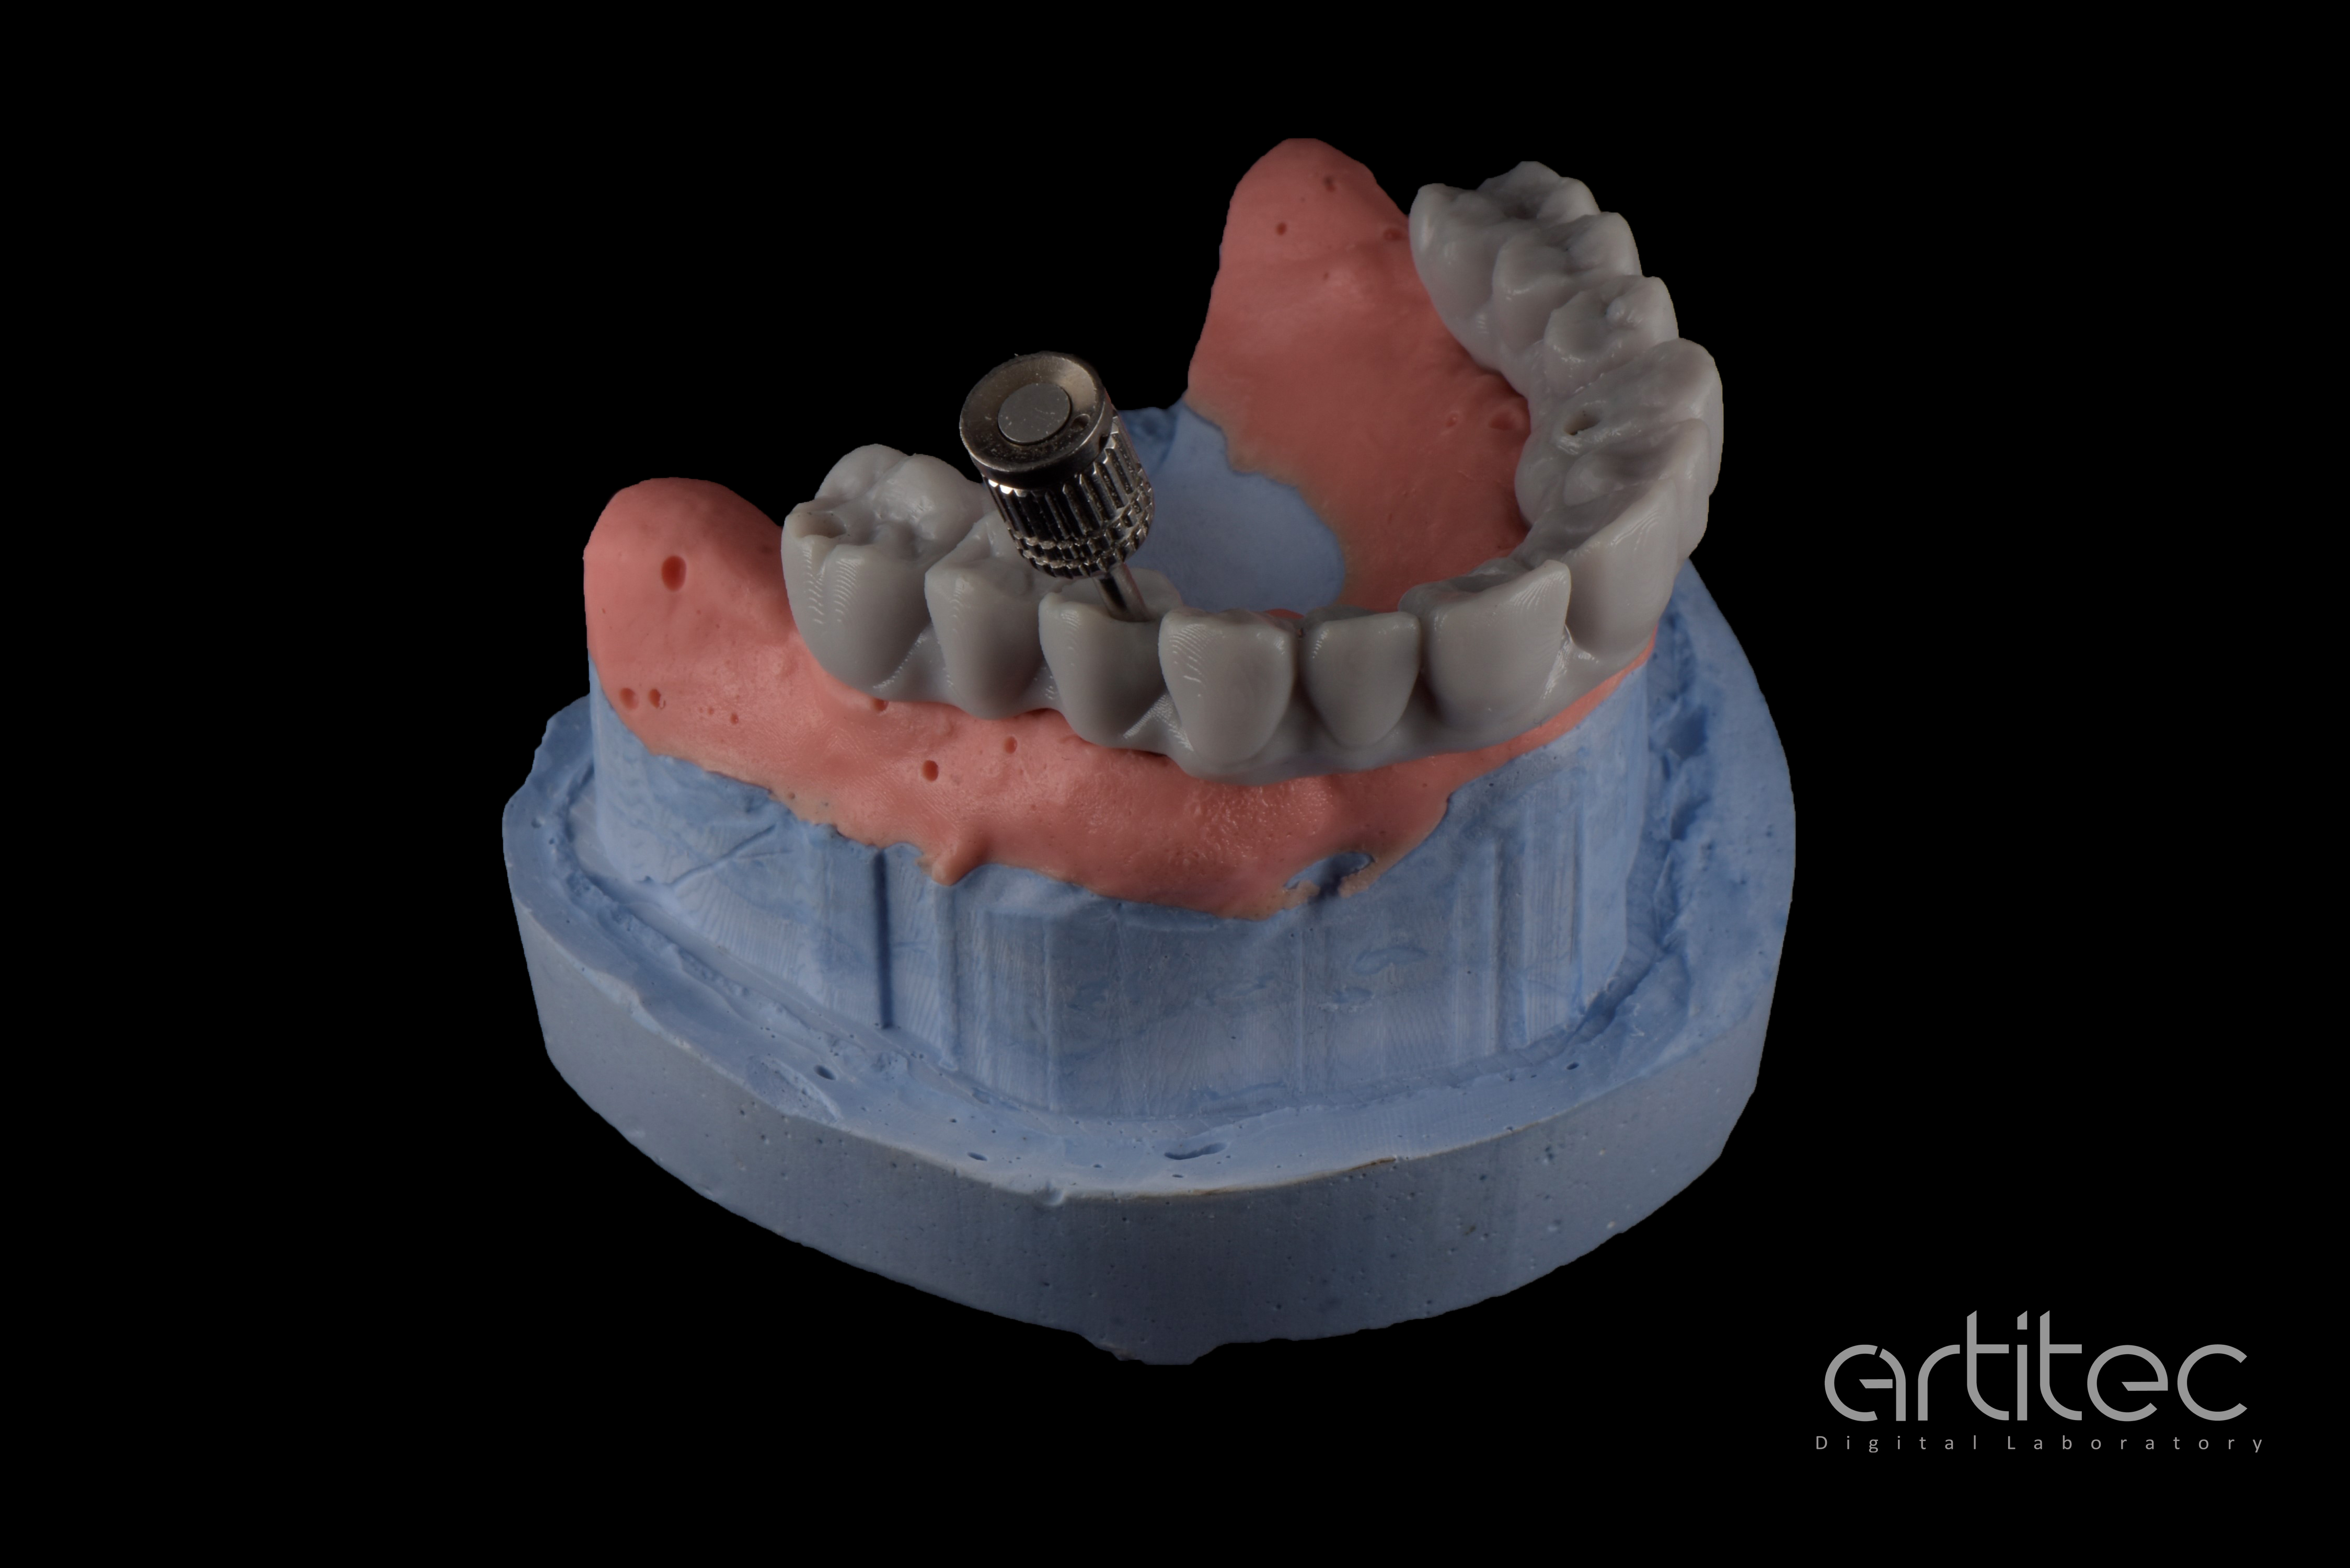

Fig. 22 Controllo e test di avvitamento su modello ibrido

Fig. 23 Registrazione dei profili di emergenza del provino da stampa 3D

Fig. 24 Ulteriore provino da stampa 3D per visione estetica

Fig. 25 Index in CrCo laser melting per verifica e congruità della posizione implantare

Fig. 26 Barra Hi-Fiber posizionata sui linker

Fig. 27 Dettaglio della barra Hi-Fiber posizionata sui linker